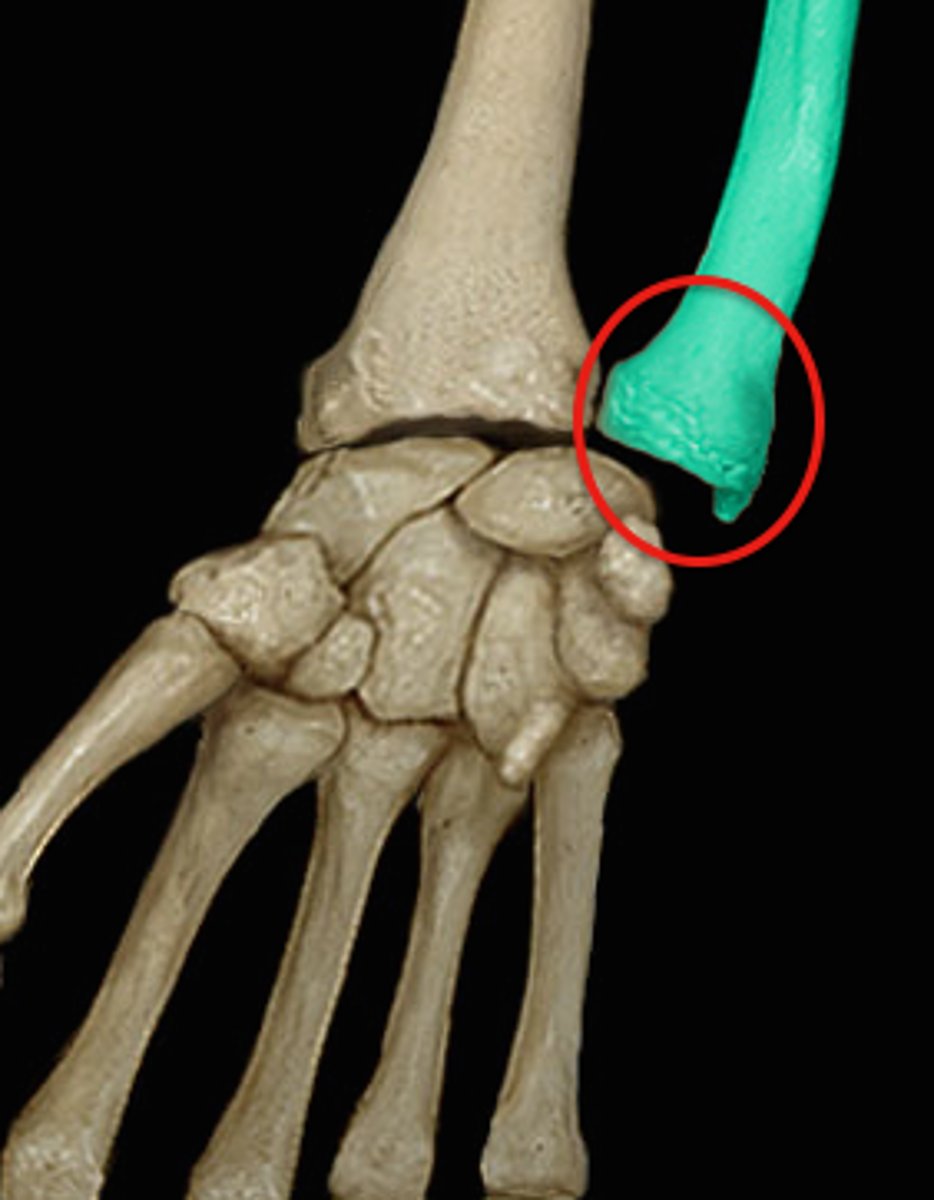

Pisiform - Carpal

Triquetral - Carpal

Lunate - Carpal

Scaphoid - Carpal

Trapezium - Carpal

Trapezoid - Carpal

Capitate - Carpal

Hamate - Carpal